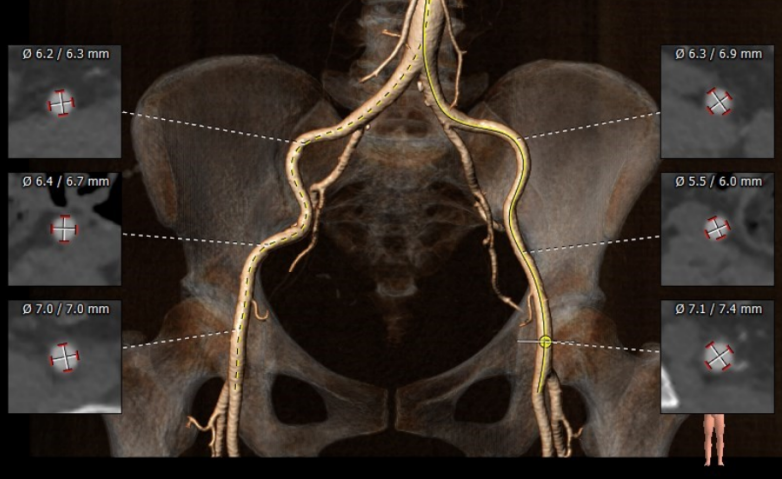

术前CT评估:

术前CT结果显示,患者主动脉瓣瓣环周长:67.4 mm,平均瓣环直径:21.5mm。左流出道平均直径20.9mm,瓦氏窦最小径31.7mm,窦管结合交界处(STJ)28.4mm,风湿性心脏病,三叶瓣,轻度钙化,瓣叶明显增厚,钙化,左冠开口高度12.2mm,右冠开口高度16.1mm,结合瓦氏窦内径,瓣叶长度及度钙化分布等综合因素考虑,冠脉风险较低,双侧入路血管直径尚可,无明显钙化,最小直径为5.5mm。

主动脉根部评估

冠脉阻挡风险评估及钙化程度分析

外周血管入路评估